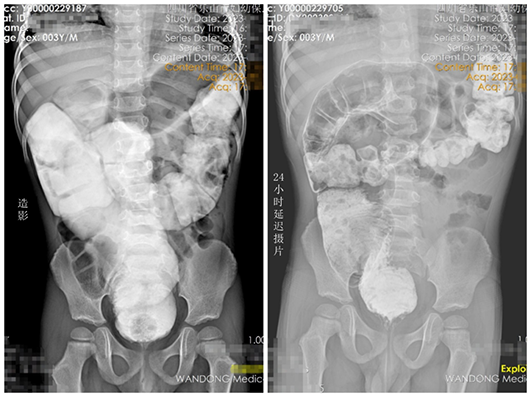

該患兒3歲,因長期頑固性便秘伴腹脹輾轉(zhuǎn)就診于當(dāng)?shù)囟嗉裔t(yī)院,均無明顯改善。遂前往我院小兒外科就診,通過詳細(xì)詢問患兒病史、仔細(xì)查體,并完善造影后考慮先天性巨結(jié)腸可能?;純航?jīng)灌腸治療后入院,直腸粘膜活檢證實(shí)為先天性巨結(jié)腸。在我院院長、小兒外科學(xué)科帶頭人包平倩的帶領(lǐng)下,小兒外科團(tuán)隊(duì)為其成功實(shí)施腹腔鏡下先天性巨結(jié)腸根治術(shù)。術(shù)后患兒恢復(fù)良好,目前已治愈出院。